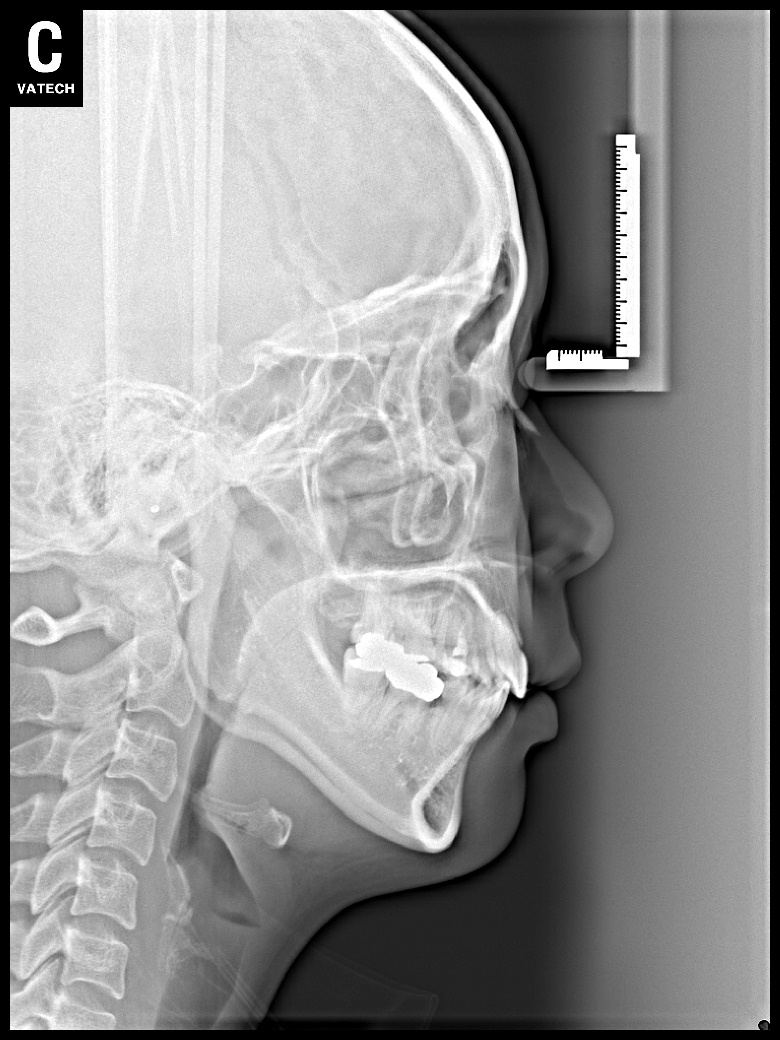

치료 전 사진입니다.